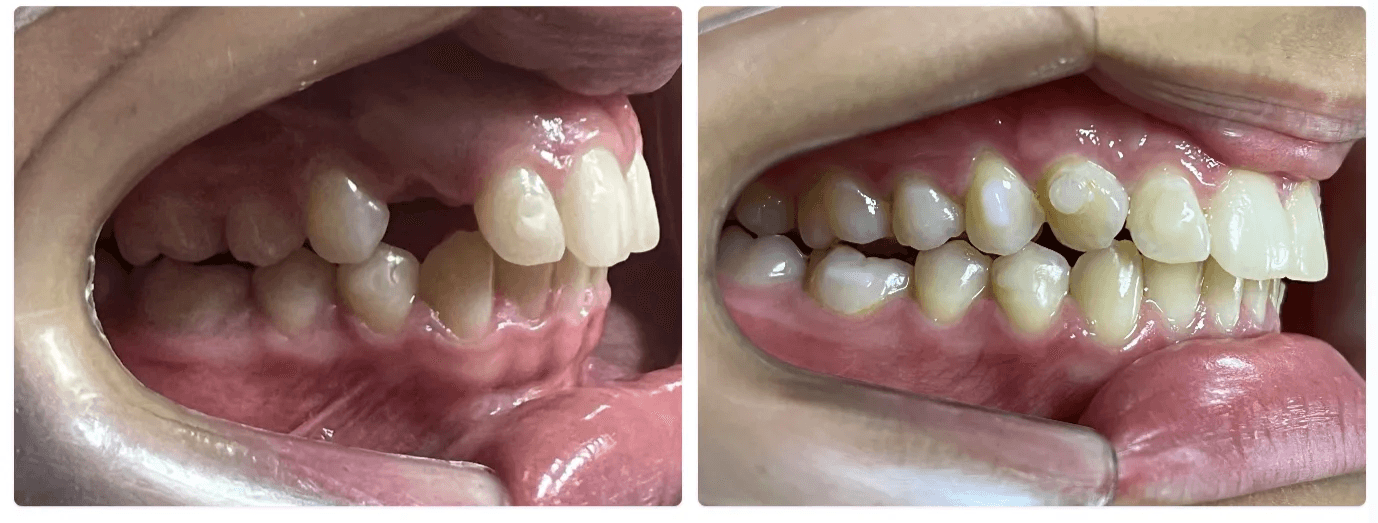

Tracionamento Dentário:

Requer forças mais significativas e direcionadas que os alinhadores sozinhos podem não ser capazes de fornecer sozinhos, com isso, se faz necessário uso de mecânicas auxiliares.

Pode ser feito mas requer um ortodontista experiente para saber direcionar corretamente a movimentação e acessar o dente.

O eixo de saída do dente é muito importante, assim como idade do paciente.

Verticalização de Raízes:

É um movimento que requer muita força, geralmente relacionada a utilização de attachments, elásticos, power arms e mini implantes. Quanto maior a raiz do dente e menos ancoragem o alinhador tiver relacionado aquela área, mais imprevisível o resultado.

Verticalização de molares só tem alguma previsibilidade se for associado a distalização, o que geralmente envolve um planejamento de abrir espaço para implantes e não de tentar fechar esse espaço.

Dentes com inclinação maior que 30º mesmo utilizando mecânicas elásticas não possui previsibilidade.